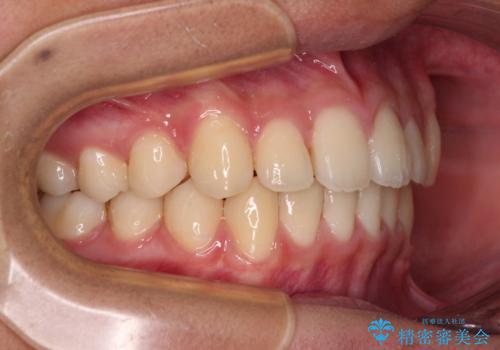

- 前歯のデコボコと隙間を気にして来院された高校生の患者様です。

下顎前歯が上顎前歯を突き上げるような咬み合わせとなっており、その影響で上顎正中に隙間ができている状態でした。

叢生の程度は軽度であり、本人もしっかりと使用する自信があるとのことだったので、インビザラインによる矯正治療を行うこととしました。

突き上げによる隙間を予防する為に、深い咬み合わせを改善するような治療計画としました。咬み合わせを改善させることはできましたが、隙間は後戻りしやすいので、通常の下顎前歯のみではなく、上顎前歯2本もワイヤーで保定を行いました。